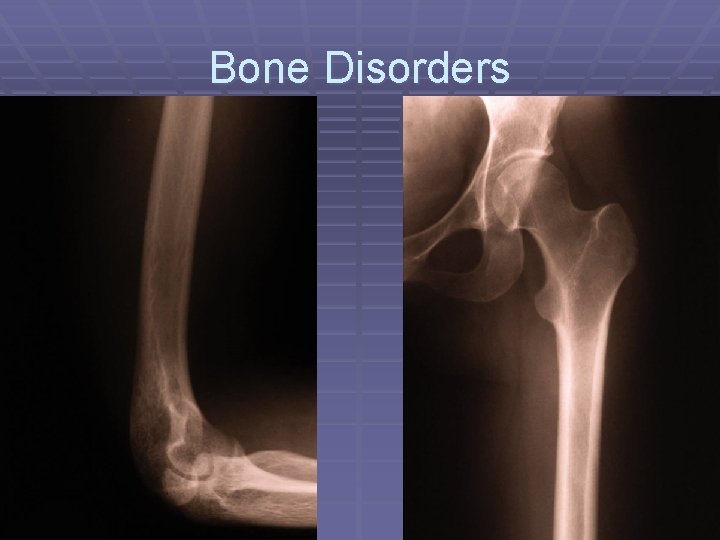

Bone Disorders

Osteoporosis

Osteomalacia (Rickets)

Paget’s Disease trabeculae Paget’s x-ray Normal xray

Histiocytosis

Osteomyelitis